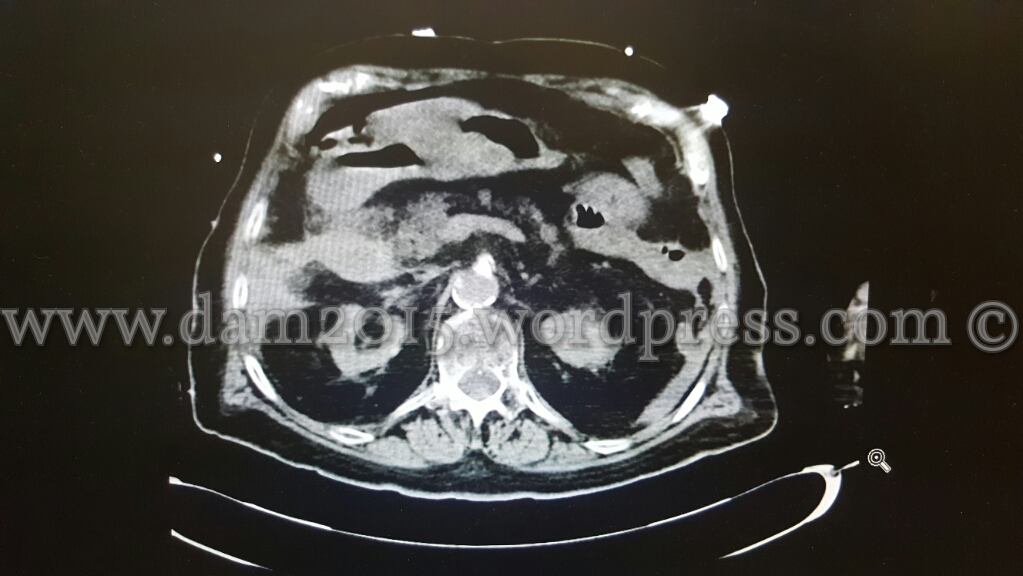

Eseguita TC addome con MDC che mostra aria libera intraperitoneale disposta prevalentemente anteriormente al fegato ed al corpo gastrico, come da perforazione di viscere cavo.

Evidente inoltre marcato ispessimento parietale dell’antro gastrico, della I e II porzione duodenale e del tratto medio-distale dell’esofago (che rimane beante lungo tutto il suo decorso) con edema periviscerale .

Falde di versamento periepatico, tra le anse intestinali, in sede perisplenica e nello scavo pelvico.

Reperto collaterale di marcata calcificazione dei vasi splenici.